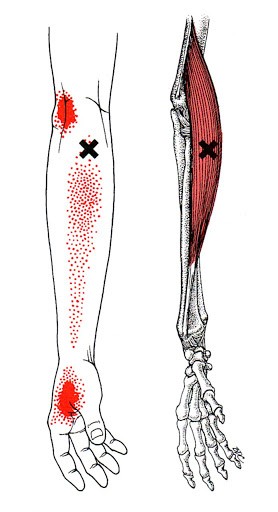

위 그림들에 붉게 표시된 부분이 해당 근육에 문제가 생겼을 때 통증을 일으키는 부위입니다. 교통사고 혹은 낙상과 같이 심각한 급성 사고가 아니라면 "뼈"에 통증을 호소하기에는 무리가 있고 아마도 근육의 과도한 사용으로 인해 트리거포인트가 방사통을 뿜어내는 것이 아닌가 생각됩니다.

이를 해결하기 위해서는 충분한 마사지가 필요한데요,

위와 같이 팔을 위치시키고 무릎(정확히는 정강이뼈)과 체중을 이용해 전완을 충분히 마사지해줍니다.